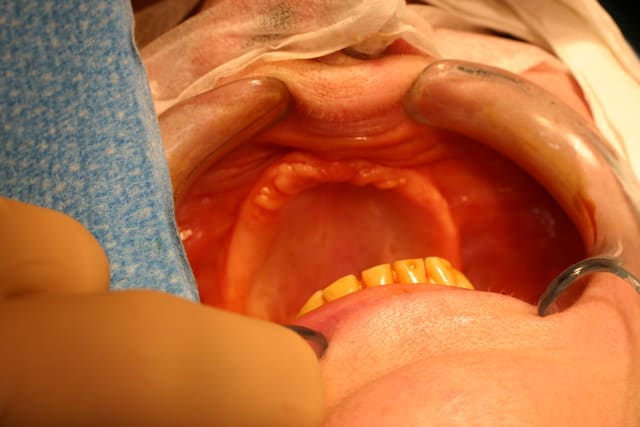

Regarde l aspect de la muqueuse palatine en regard des plaques zygomatiques : rose ferme et dure...avec interpore ce serait rouge un peu mélasse... Le nanobone est la vraie clé qui a changé ma vie d implanto basal

On ne dirait pas la même crête et pourtant il s agit bien de la patiente en préop et 18 mois plus tard...

Quel changement de volume et de qualité tissulaire...

qd tu vois la transformation tissulaire au niveau du volume et de la qualité des muqueuses avant-après, je doute très fort que ce soit une muqueuse diapneusique comme tu le laissais entendre...